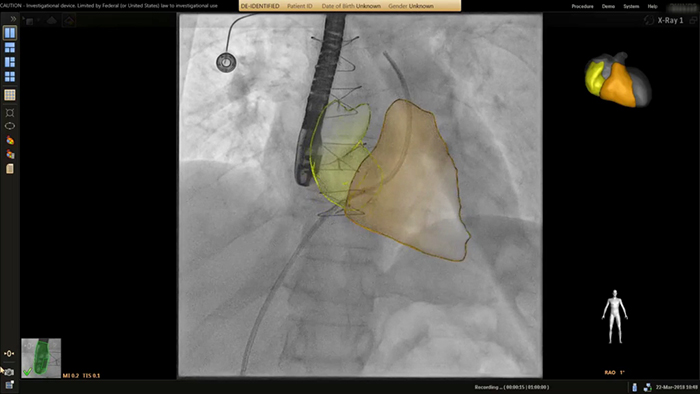

Marcación de la zona anatómica objetivo en TSM Pro

Guía de colocación de stent en coartación aórtica con VesselNavigator